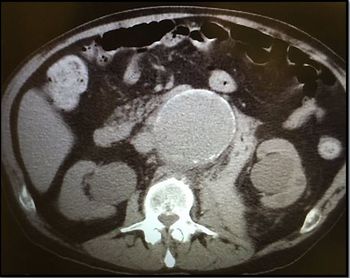

A 47 y/o woman with cirrhosis, HCV, and chronic pancreatitis requests Demerol for the worst abdominal pain she has ever had. What's your diagnosis?

A 38-year-old woman has had abdominal pain x4 days that worsens on hip flexion. Imaging, labs are inconclusive. But there was that urine culture ...